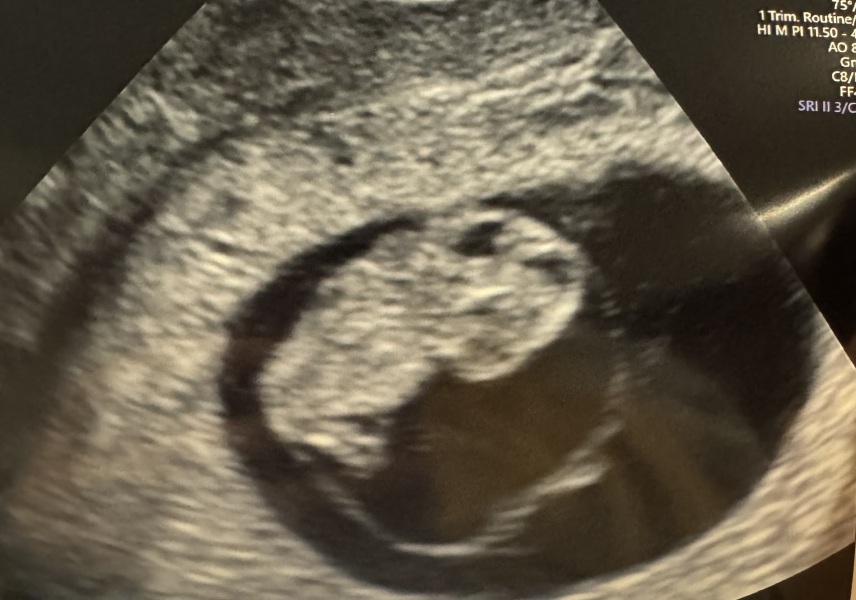

ToeBeans24 · 24/05/2024 22:44

Had my early scan today! Measured at 8w3d which I’m really pleased with. 9w1d using LMP but I know I ovulated later. Was so worried that would make me measure loads behind and cause panic. So I’m happy only 5 days different. Only 1 baby in there 🤭. Although with the bloat I look 4 months.

Hope you’re all doing ok 🤗 x

Here you go @Plumchumm 🥹🥹

i got a video too and keep playing it over and over. How are you? Xx

@ToeBeans24 There’s the wee babby, how cute is that!!!! Do you have any names picked out yet? I have a list since before I even got pregnant 😂